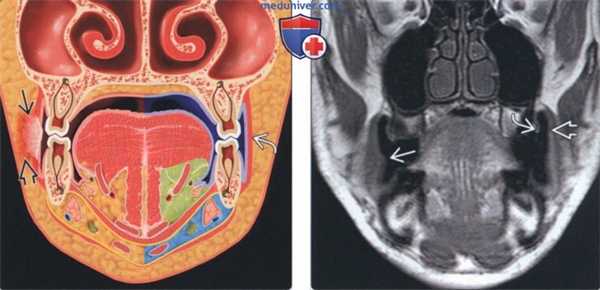

(Слева) На рисунке в корональной плоскости показан плоскоклеточный рак (ПКР) слизистой оболочки щеки на стадии Т2 (2-4 см) с инвазией подлежащей щечной мышцы и подкожною жира. При инвазии кожи щеки стадия опухоли повышается до Т4. Обратите внимание на нормальную щечную мышцу слева.

(Справа) На корональной MPT (Т1 ВИ) с использованием метода «надутых щек» определяется смещение щеки относительно слизистой оболочки десны. Визуализируются едва различимые узлы в слизистой оболочке щеки справа в, представляющие собой ПКР Признаки глубокой инфильтрации не определяются.